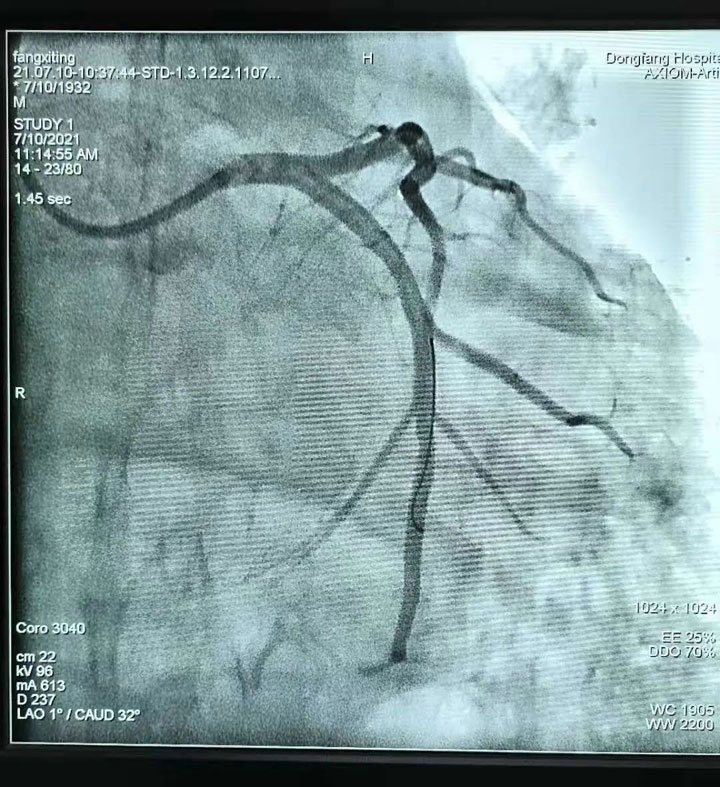

胸痛中心团队医生——心血管内科副主任王其虎、医生宁伟、熊堂鹏为患者施行了急诊冠状动脉造影+取栓术。术中造影发现患者心脏回旋支中端血管完全闭塞,大面积心肌没有血供,医生紧急使用取栓装置由远至近多次抽吸血栓,完成血运重建。“我们采用的这种取栓装置可以直接将大的血栓全部吸出体外,人体内将不再残留小血块,大大降低产生并发症的几率。”心血管内科医生熊堂鹏介绍说,这项技术可以免去冠脉支架的植入,即“介入无植入”,为广大冠心病患者提供了更加安全、有效的治疗手段。